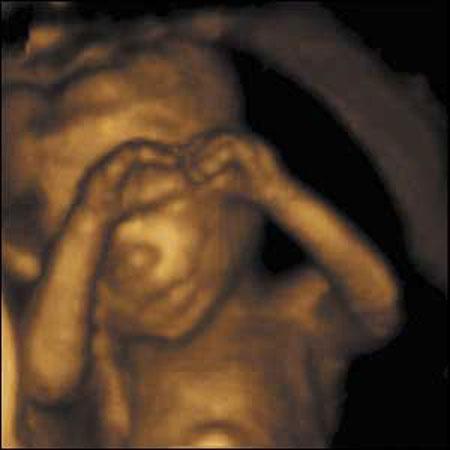

Ультразвуковые съёмки аборта на 12 неделе явно показывают: ребёнок чувствует боль, как любой из нас, и прекрасно понимает, что его хотят убить - он всеми силами старается отодвинуть от себя инструмент и широко раскрывает рот в безмолвном крике, когда у него отрывают сначала ноги, затем часть туловища…

Голову извлекают в последнюю очередь и лицо убитого ребёнка всегда искажено гримасой боли и ужаса. По этим кадрам видно, что практически нет разницы, убить ли 3-месячного ребёнка в утробе или отрезать руки -ноги -голову 5-летнему малышу. Без анестезии и в полном сознании.

- Фильм американского врача Бернарда Нэйтансона, названный «Безмолвный крик», показал всему миру, что такое аборт на сроке 11 недель беременности. Многие врачи и медсестры, посмотрев фильм, прекратили участвовать в абортах.

Это документальный фильм, и авторы рекомендуют соблюдать осторожность при его показе, поскольку некоторые кадры могут вызвать у человека психологический шок: безмолвный крик внутриутробного младенца, искаженное от боли лицо ребенка, погибающего на наших глазах...

Из закадрового текста к фильму: «Инструмент еще не коснулся ребенка, но он уже возбужден, его сердечные удары учащаются и достигают приблизительно 200 ударов в минуту. Вакуум-кюретка нащупывает ребенка, и он широко раскрывает рот в безмолвном крике».